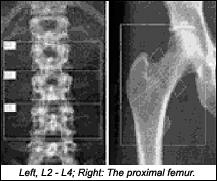

Dual-energy X-ray absorptiometry (DXA) is a relatively inexpensive measurement for bone density. DXA provides information about bone density and fracture risk. Diagnosis is based on calculated T-scores:

The problem is that as with all modalities, including radiology, DXA is operator-dependent. I don't want to use too many statistics or principles of physics in this article, but there are certain simple facts worth knowing. First, DXA uses X-rays at two energy levels to determine the bone mineral content. This is done by subtracting the difference of the absorption of X-rays between soft tissue and calcified bone. The software program calculates the bone mineral density (BMD) by dividing the bone mineral content by the area of the region of interest (e.g., an area in the spine or neck of the femur). The BMD measured by the program is compared to reference data specific to the scanner that determines the T- and Z- scores.

Thus far, we have only discussed the T- and Z- scores; but what are the other problems? One is that the positioning for DXA in the hip and spine are of vital importance. Errors can be made in the placement and sizing of the regions of interest, affecting the accuracy of the data. If the region of interest is too large, for example, the BMD will be calculated too low - or the opposite. (BMD is calculated by dividing the bone mineral content by the area measured.) Overlying material in the region of interest, such as degenerative osteophytes, can create added density, resulting in inaccurate bone density measurements.